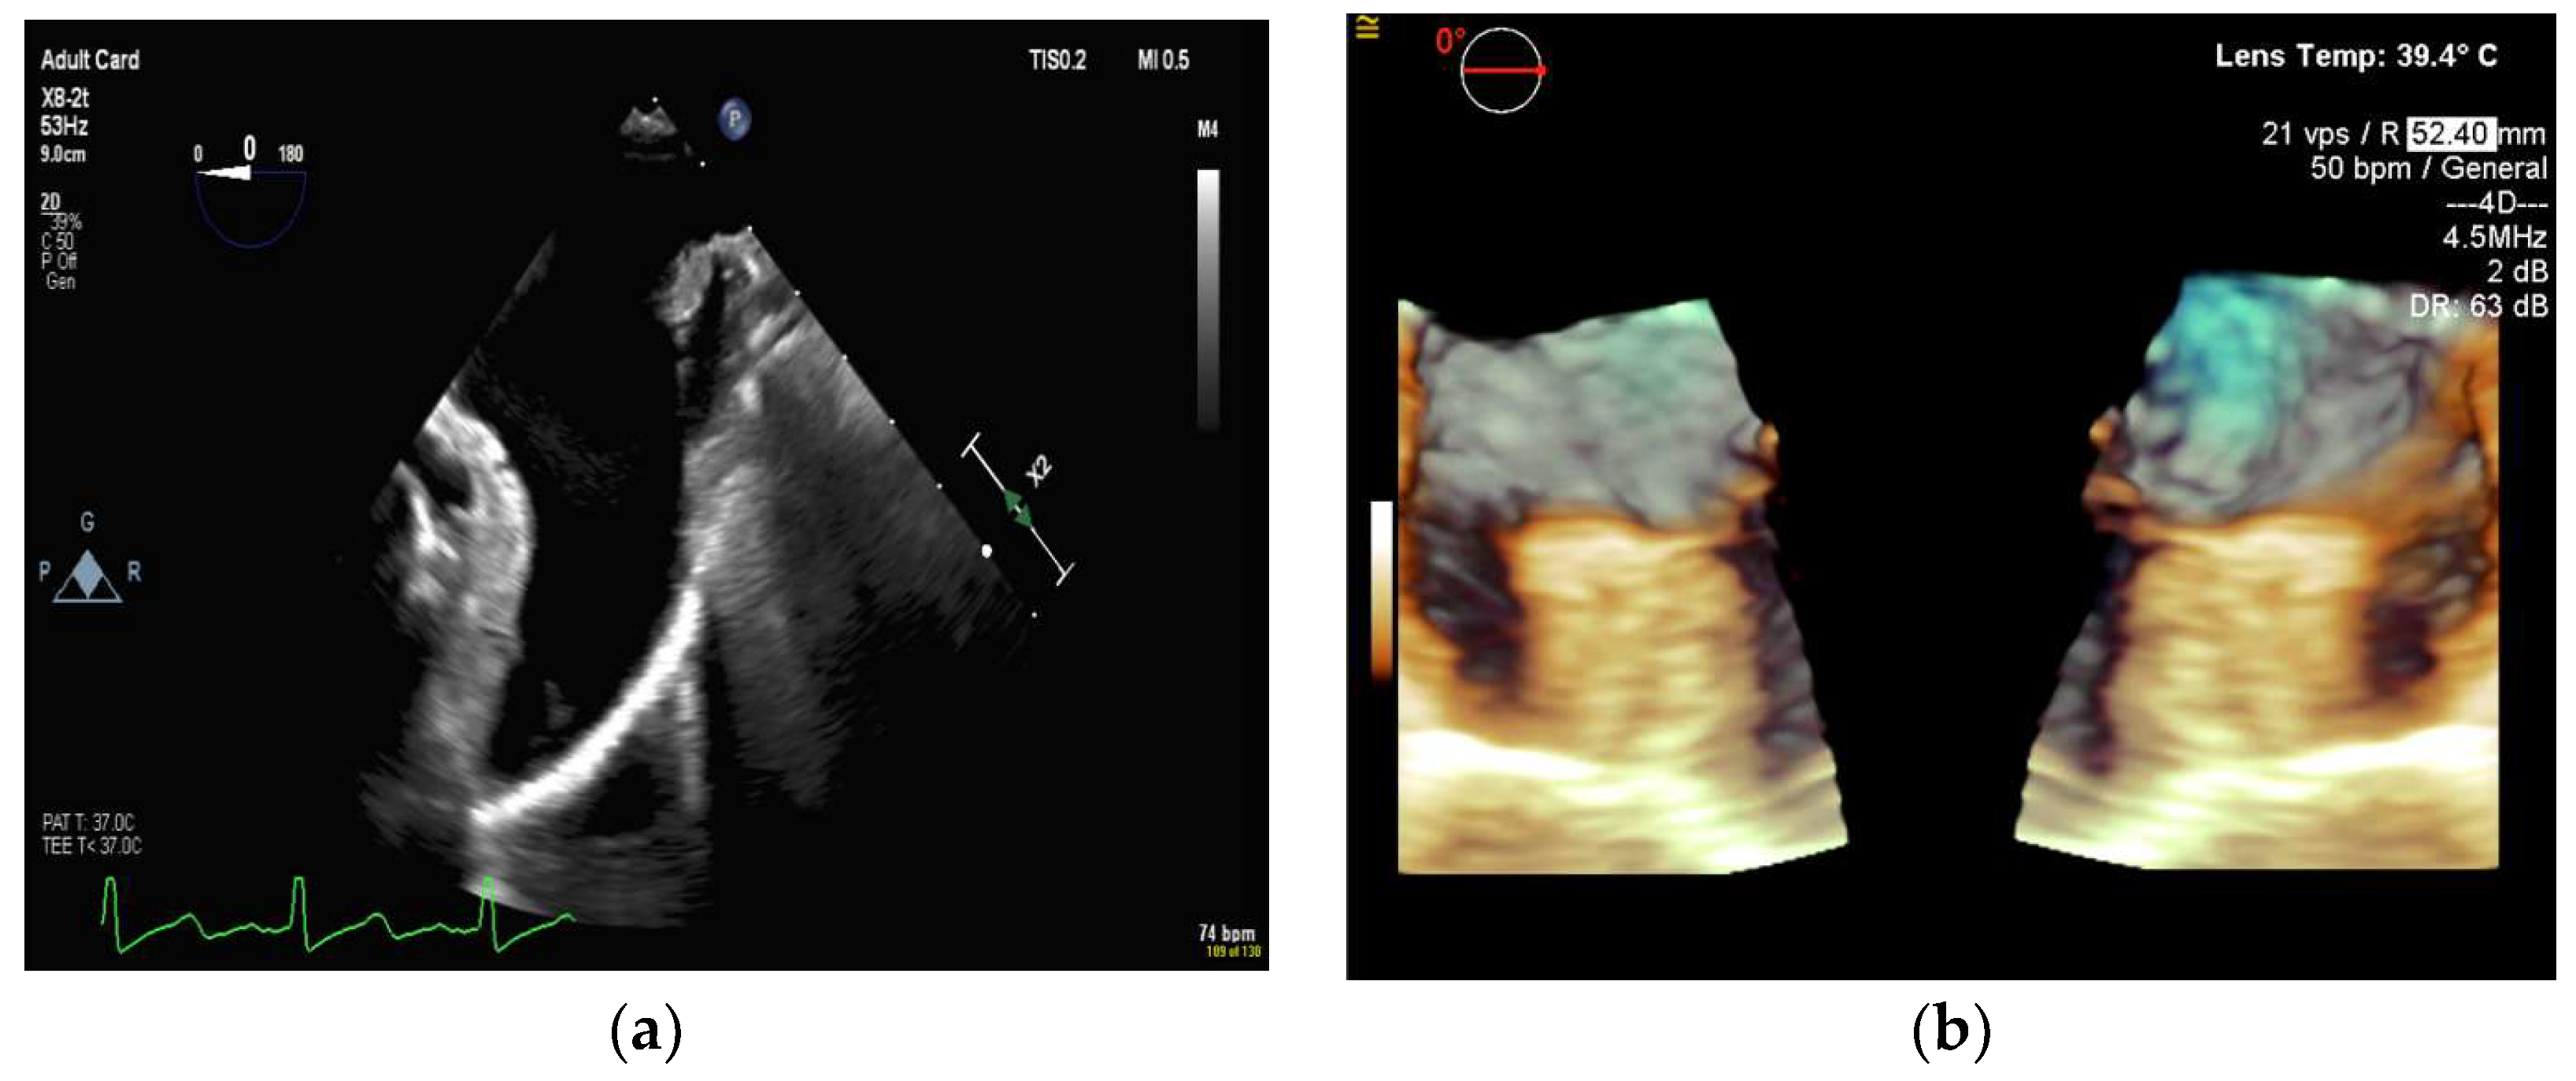

4.2.2. Left Atrial Appendage Occlusion

4.2.3. Mitral Valve Repair